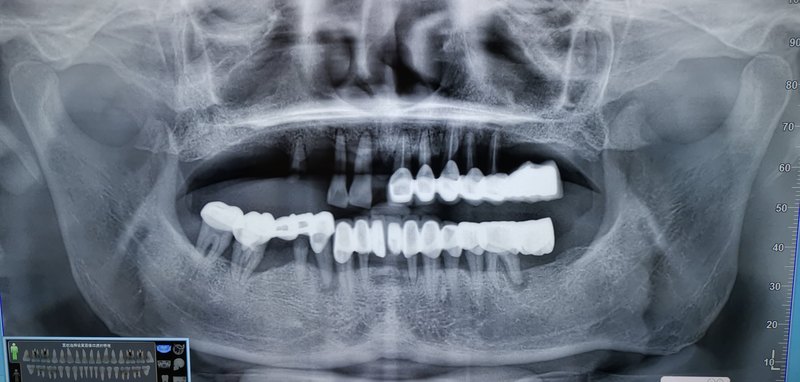

牙周病,是導(dǎo)致牙齒松動(dòng)缺失的最主要原因! 年僅48的大哥,幼時(shí)多顆蛀牙缺損,做了幾乎全口的烤瓷牙,因?yàn)榭谇恍l(wèi)生欠佳,牙結(jié)石多,導(dǎo)致牙齒松動(dòng),沒有保留價(jià)值的,給予拔除! 那么,針對這種情況,有條件的,首選種植牙修復(fù)。門診局部麻醉下,不切開,不翻瓣,微創(chuàng)植入六顆種植體。 拍片提示種植體位置良好,復(fù)合基臺(tái)就位,準(zhǔn)備即刻負(fù)載 臨時(shí)基臺(tái) 臨時(shí)的塑料牙,有點(diǎn)白 從有牙到無牙 經(jīng)歷了數(shù)十年 從無牙到有牙 兩個(gè)小時(shí) 即刻種植修復(fù)即刻負(fù)載!